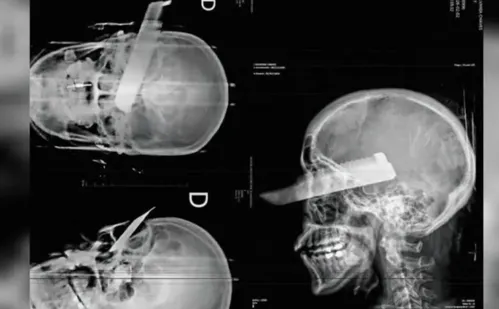

A vítima, 41, foi atingida por uma faca no olho direito quando tentava fugir |  Foto: Divulgação/Polícia Civil SC

A vítima, 41, foi atingida por uma faca no olho direito quando tentava fugir. Segundo a Polícia Civil, o suspeito teria iniciado as agressões por volta das 8h na casa do casal, que fica na Linha Marcelino, uma zona rural da cidade.

A faca teria entrado pelo lado direito do crânio e atravessado pela órbita ocular direita. Ainda de acordo com a corporação, ela foi levada ao hospital Padre João Berthier com o objeto alojado e hemorragia ativa. O UOL entrou em contato com a unidade de saúde para saber o estado de saúde dela e aguarda retorno.